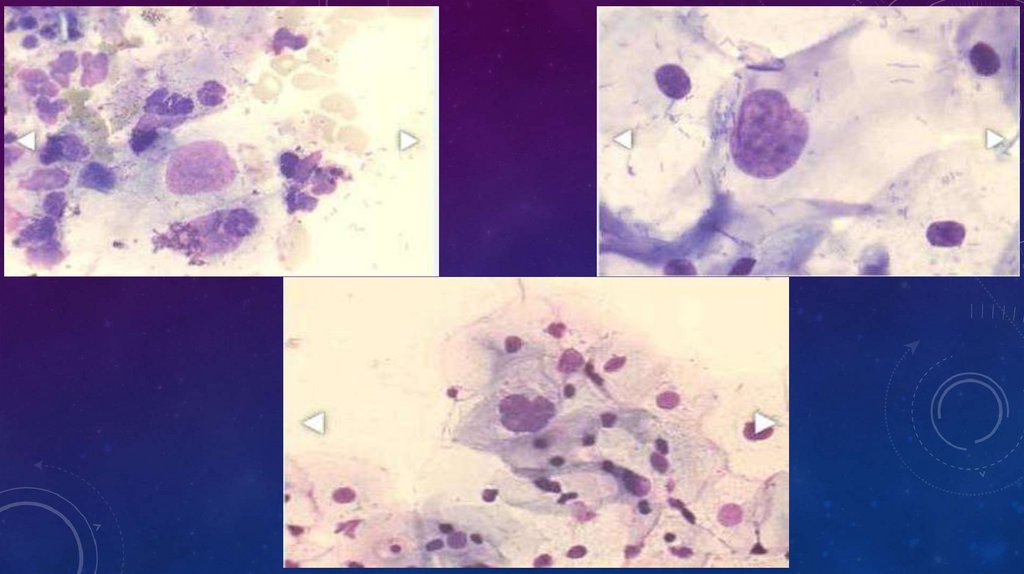

ПЛОСКОКЛЕТОЧНАЯ КАРЦИНОМА С

ОРОГОВЕНИЕМ